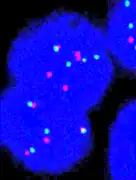

Fluorescence in situ hybridisation

FISH can be used to measure the number of copies of the gene which are present and is thought to be more reliable than immunohistochemistry.[45] It usually uses chromosome enumeration probe 17 (CEP17) to count the amount of chromosomes. Hence, the HER2/CEP17 ratio reflects any amplification of HER2 as compared to the number of chromosomes. The signals of 20 cells are usually counted.

This cell displays 2 signals of HER2 (red) and 3 signals of CEP17 (green)

Two signals that are closer to each other than the signal diameter count as one.

One of these signals is too faint, and is presumably debris.

Cells with only one type of signal are excluded from the count.

Overlapping cells are also excluded from the count.

A yellow signal counts as one red and one green (which are overlapping)